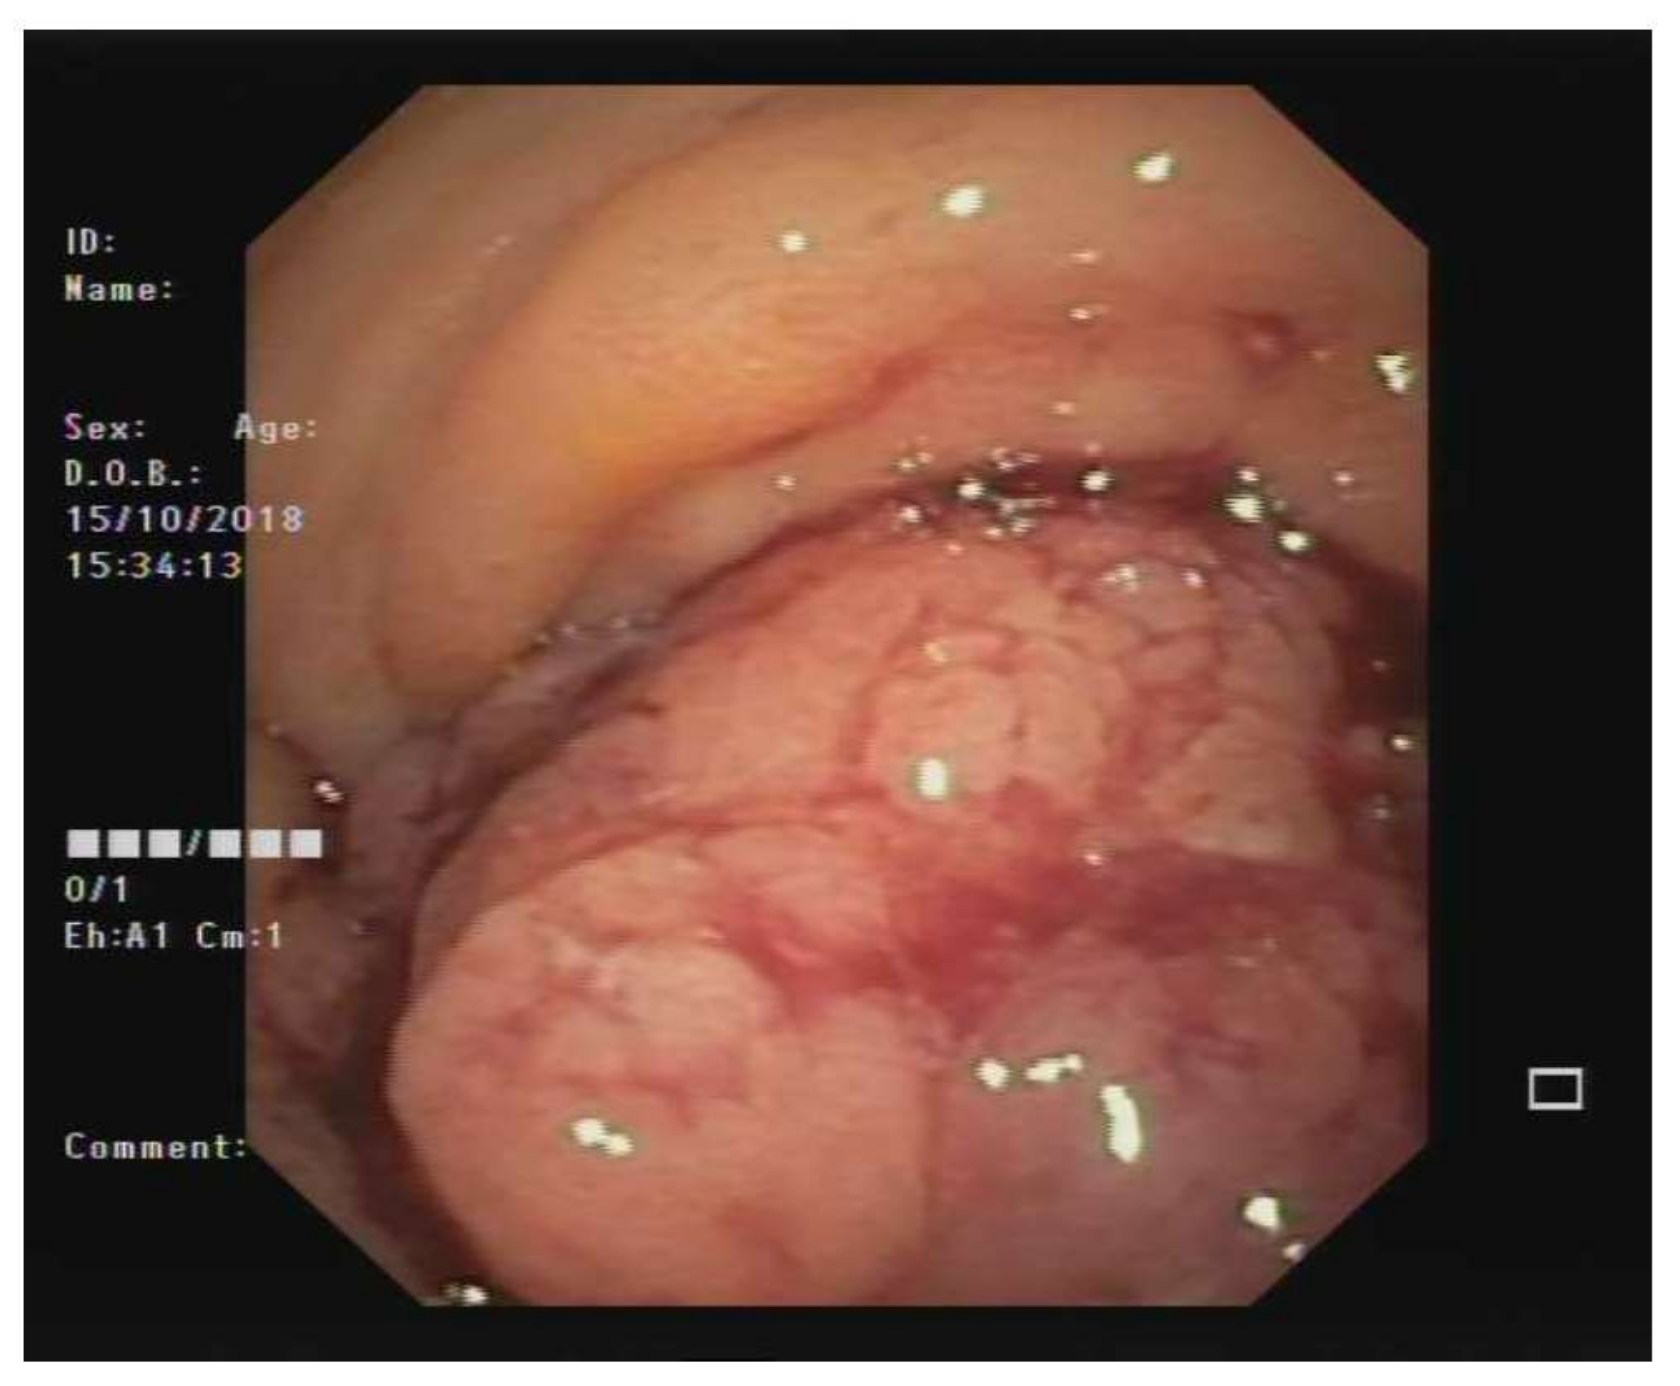

After an open biopsy of the nodal mass, the pathology revealed lymph-node metastasis from epithelial neoplasia, while the analysis of the peritoneal fluid, collected during surgery, revealed the presence of neoplastic cells. Colonoscopy revealed a large polypoid mass of the sigmoid colon, measuring about 5–7 cm in diameter and lying about 20 cm from the anal verge. The lesion almost completely occluded the colonic lumen, allowing a small endoscope (diameter 4.9 mm) to pass, albeit with some difficulty (Figure 2). Multiple biopsies were performed, with the pathology revealing undifferentiated adenocarcinoma (Figure 3). An evaluation of tumor markers showed a high level of carbohydrate antigen (CA) 19-9, 330 UI/mL (normal value < 37 UI/mL) while carcinoembryonic antigen (CEA) levels were normal.

Figure 3. Histology. (a) Hematoxylin and eosin staining at 20× magnification showing fragments of colic mucosa in which there are foci of cells with atypical, polymorphic and polymetric nuclei, hyperchromic and sometimes nucleolated, coherent, with poorly differentiated carcinoma- (b) Immunohistochemical staining for CK CAM5.2 of the neoplastic cells at 20× magnification. Scale bar 200 µm.